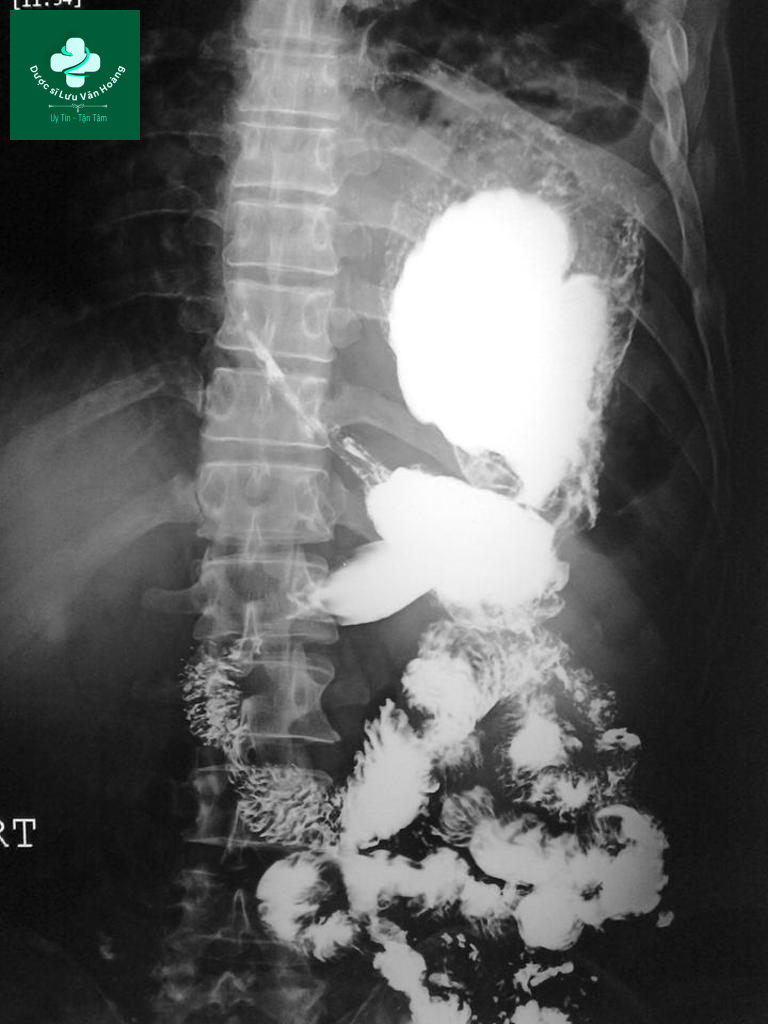

- Case 1: vỡ cơ hoành sau chấn thương với tạng thoát vị là dạ dày và có xoắn dạ dày.

Phim chụp cho thấy gián đoạn cơ hoành trái với tạng thoát vị là dạ dày lên lồng ngực. Dạ dày xoắn theo trục tạng.